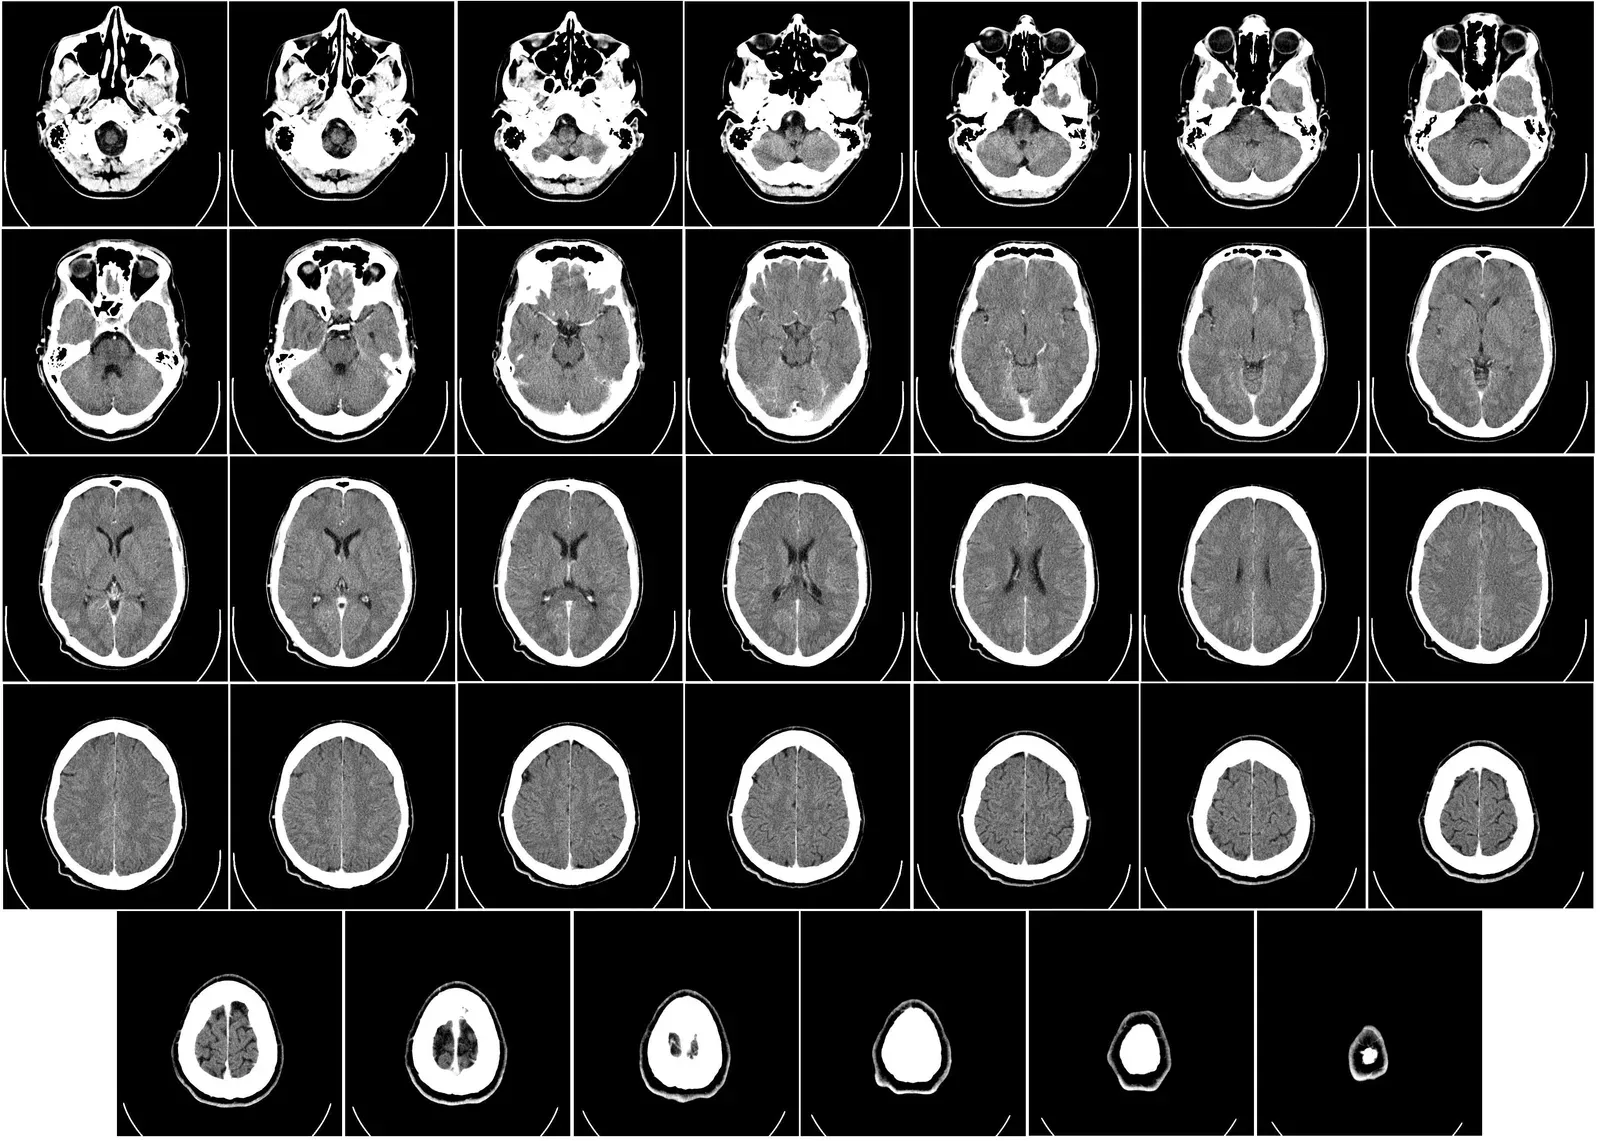

One of the most surprising clues about lifelong brain change came from studies of older adults whose brains were examined after death. Some of these people had the tangled proteins and plaques typically linked to dementia, yet during life they showed little or no memory loss. Their brains seemed to have built up a kind of cognitive reserve, a hidden buffer that helped them function despite damage that, on a scan, looked alarming. That reserve did not appear by magic; it was associated with years of mental stimulation, social connection, and learning.

When neuroscientists looked closer, they saw that aging brains could sprout new connections between neurons, strengthen existing pathways, and recruit fresh regions to handle demanding tasks. In one sense, the older brain behaved like a city that has lost a major bridge but reroutes traffic through side streets and newly built overpasses. The routes may be different from those in youth, but they can still get you where you need to go. That flexibility is the essence of neuroplasticity, and it does not suddenly switch off at age forty, sixty, or even eighty.

Modern imaging techniques, from high‑resolution MRI to tools that track blood flow and electrical activity, flipped that old script. Again and again, researchers saw adult brains reorganize after stroke, injury, or intense training, sometimes in as little as a few weeks of practice. Experiments in which adults learned to juggle, navigate complex virtual cities, or take up musical training late in life all showed structural and functional changes in key brain regions. Instead of a finished statue, the brain started looking more like a clay model that stiffens with age but can still be reshaped with enough consistent pressure.